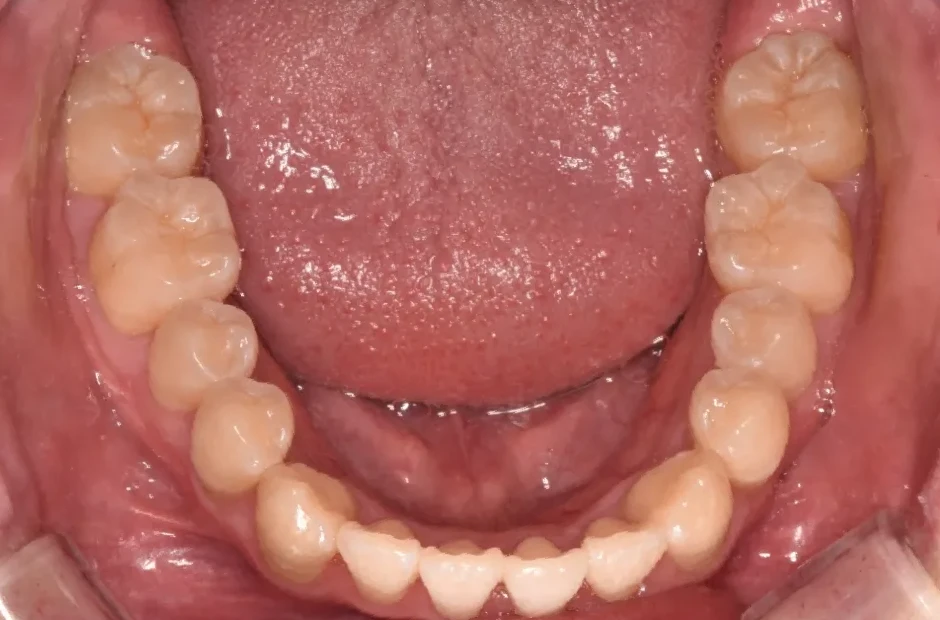

治療前